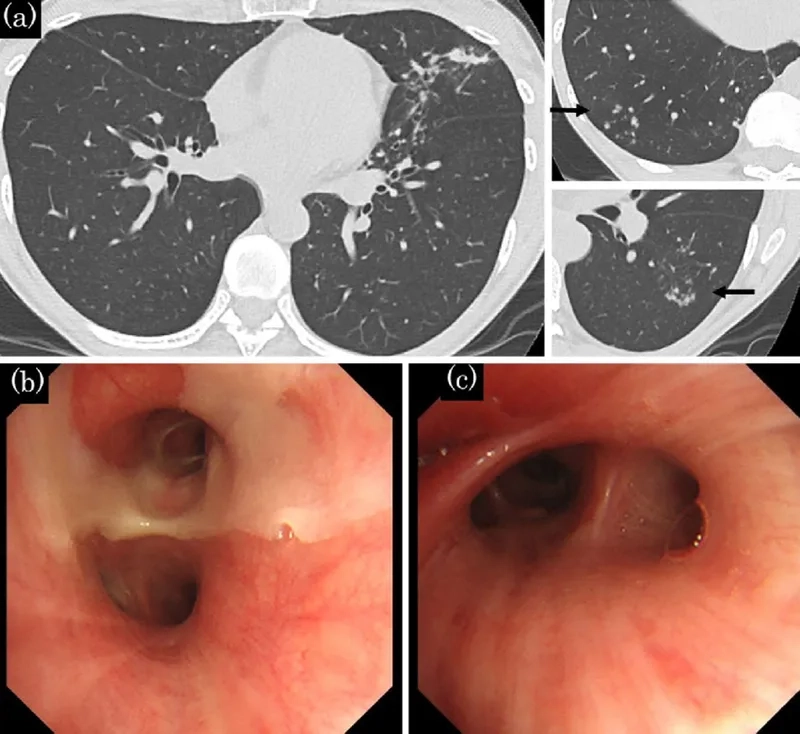

• Bronchiectasis is a disease where the lung's airways become permanently damaged and widened, making it difficult to clear mucus and leading to infections.

Diagram of lungs with Bronchiectasis